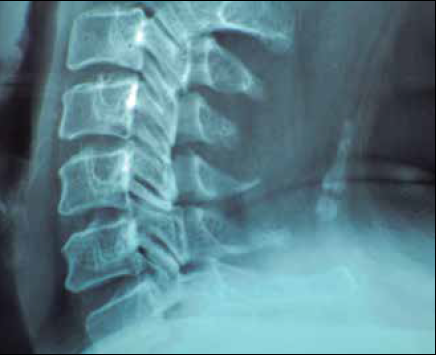

Figura 1 Radiografía lateral de columna cervical que muestra osificación heterotópica (miositis osificante circunscrita) a nivel de ligamento cervical posterior de C4 a C6 en la inserción ligamentaria de los músculos trapecios en mujer de 43 años dedicada a cargar rollos de tela durante 20 años.